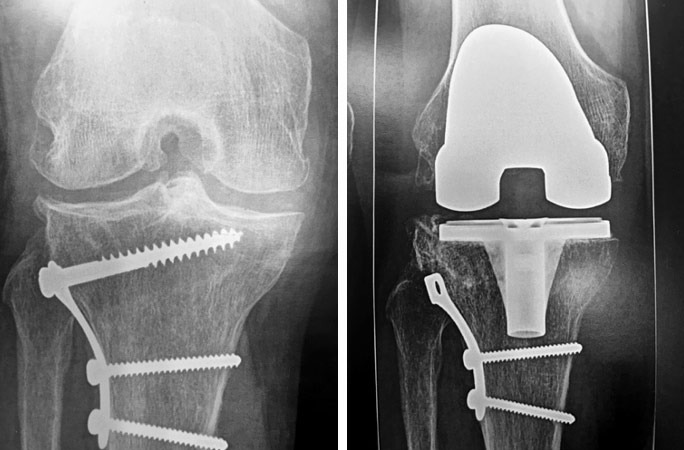

Homme 60 ans, opéré par prothèse rotulienne et prothèse uni-compartimentale interne. Toujours douloureux.

Pas d’infection.

Changement pour mettre en place une prothèse totale du genou. Aucune douleur résiduelle.